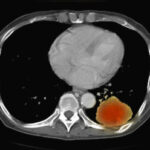

Además de la predisposición genética, la deficiencia de lactasa también puede desarrollarse como consecuencia secundaria de diversas enfermedades que afectan la mucosa del intestino delgado, en particular la porción proximal del mismo, donde se encuentra la mayor concentración de la enzima lactasa. Trastornos como la enfermedad de Crohn, la enfermedad celíaca, la gastroenteritis viral, la giardiasis, el síndrome de intestino corto y la malnutrición pueden dañar la mucosa intestinal y disminuir la producción de lactasa. En estos casos, la reducción de la actividad enzimática es secundaria a la disfunción intestinal, lo que interfiere en la absorción adecuada de nutrientes, incluida la lactosa.

Además de la posibilidad de que la intolerancia a la lactosa de inicio tardío se presente de manera similar a otros trastornos gastrointestinales, es importante destacar que la deficiencia de lactasa no siempre es una condición primaria; a menudo, se desarrolla de manera secundaria a otras afecciones gastrointestinales. La deficiencia de lactasa secundaria se produce cuando un trastorno subyacente afecta la mucosa intestinal, lo que reduce la cantidad de lactasa disponible para la digestión de la lactosa. Entre los trastornos que pueden provocar una deficiencia de lactasa secundaria se encuentran la enfermedad celíaca, la enfermedad de Crohn, las infecciones intestinales, y la radioterapia dirigida al abdomen. Estas afecciones dañan la mucosa intestinal, lo que a su vez disminuye la actividad de la lactasa, dando lugar a síntomas de malabsorción de lactosa, incluso en personas que previamente no presentaban problemas para digerir este azúcar.

Por ejemplo, en la enfermedad celíaca, el daño a las vellosidades intestinales puede llevar a una reducción en la producción de lactasa, lo que resulta en una intolerancia a la lactosa adquirida. De manera similar, en la enfermedad de Crohn, la inflamación crónica del tracto gastrointestinal, particularmente en el intestino delgado, puede alterar la capacidad de absorción de lactosa. En estos casos, la deficiencia de lactasa es un efecto secundario del trastorno subyacente, y los pacientes pueden experimentar síntomas de intolerancia a la lactosa como parte de un cuadro clínico más complejo.